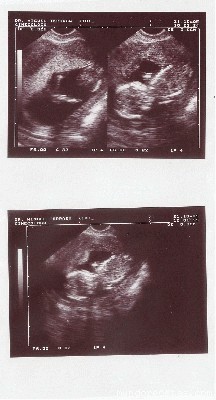

os ense?o la eco de 13 semanas:

esta es mi cosita cuando estaba de 13 semanas, asi me entere de que estaba embarazada...

que bien se ve pausan, ya se van distinguiendo las extremidades, a mi me parece que se ve c**o de frente no? a mi niña siempre la veía de perfil.